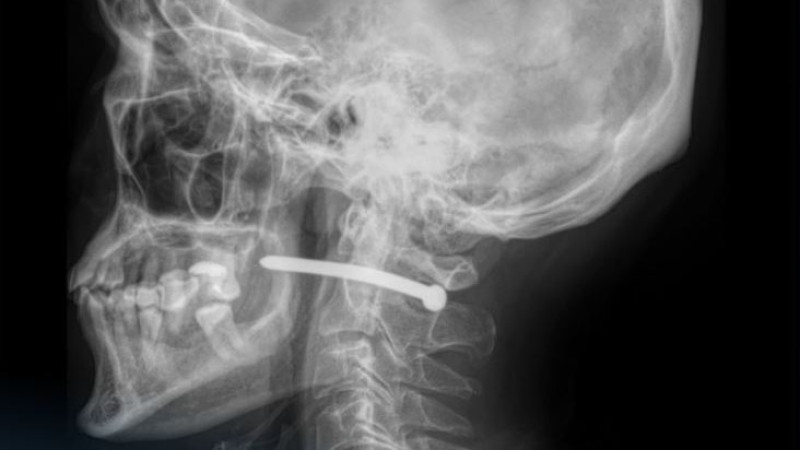

По информации из многопрофильной городской больницы скорой медицинской помощи, пострадавший обратился с раной в заушной области. Рентгеновское обследование показало, что гвоздь прошёл рядом с шейным отделом позвоночника, что создало угрозу для его здоровья.

Врачи отметили, что мужчине повезло, так как жизненно важные структуры не были повреждены. Травмы в области шеи могут быть крайне опасными из-за близости крупных сосудов, нервов и дыхательных путей.

Челюстно-лицевые хирурги успешно провели операцию: удалили инородное тело, обработали рану и наложили швы с стерильной повязкой.